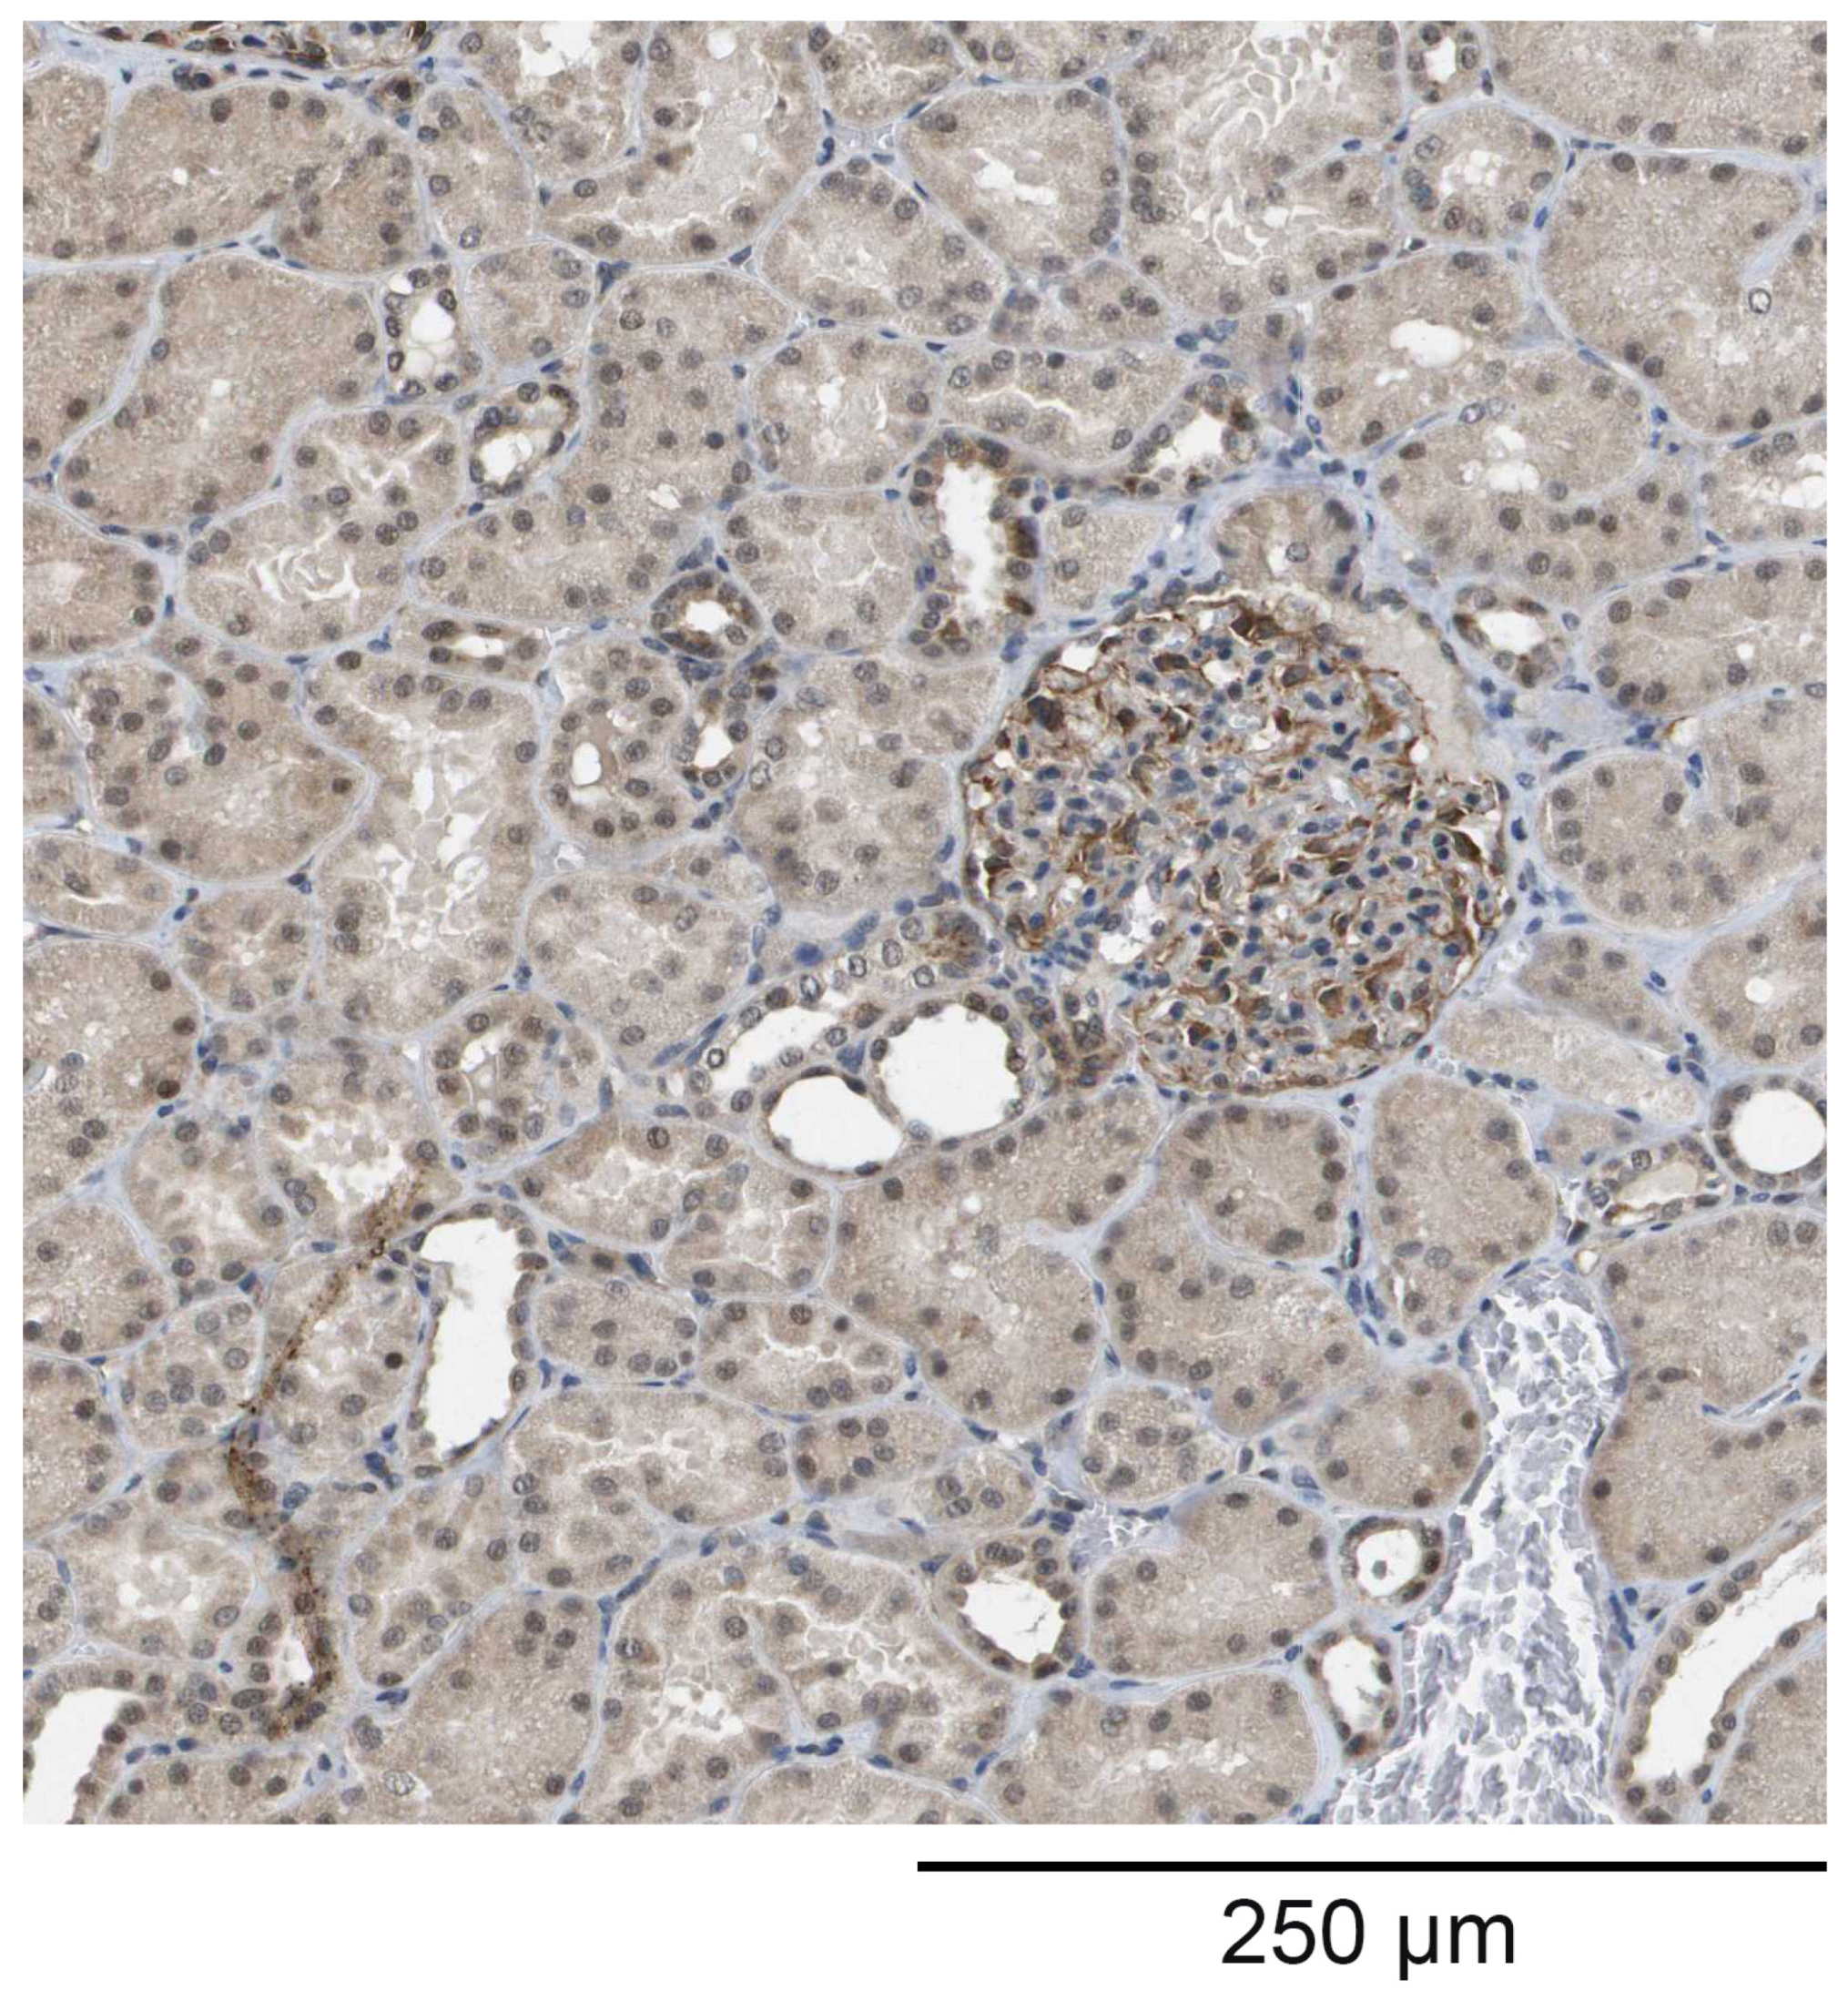

The staining of kidney tissue with the polyclonal antibodies raised against HPLBII-P showed the distinct staining of podocytes in the glomeruli (Figure 1). Weak staining was also seen in some collecting ducts, but in few tubular cells.

Figure 1.

The staining of a nephron with the polyclonal anti-HPLBII-P antibodies. Most staining is seen in the glomeruli and probably associated with the podocytes, but also in some other structures such as the collecting ducts and tubuli.